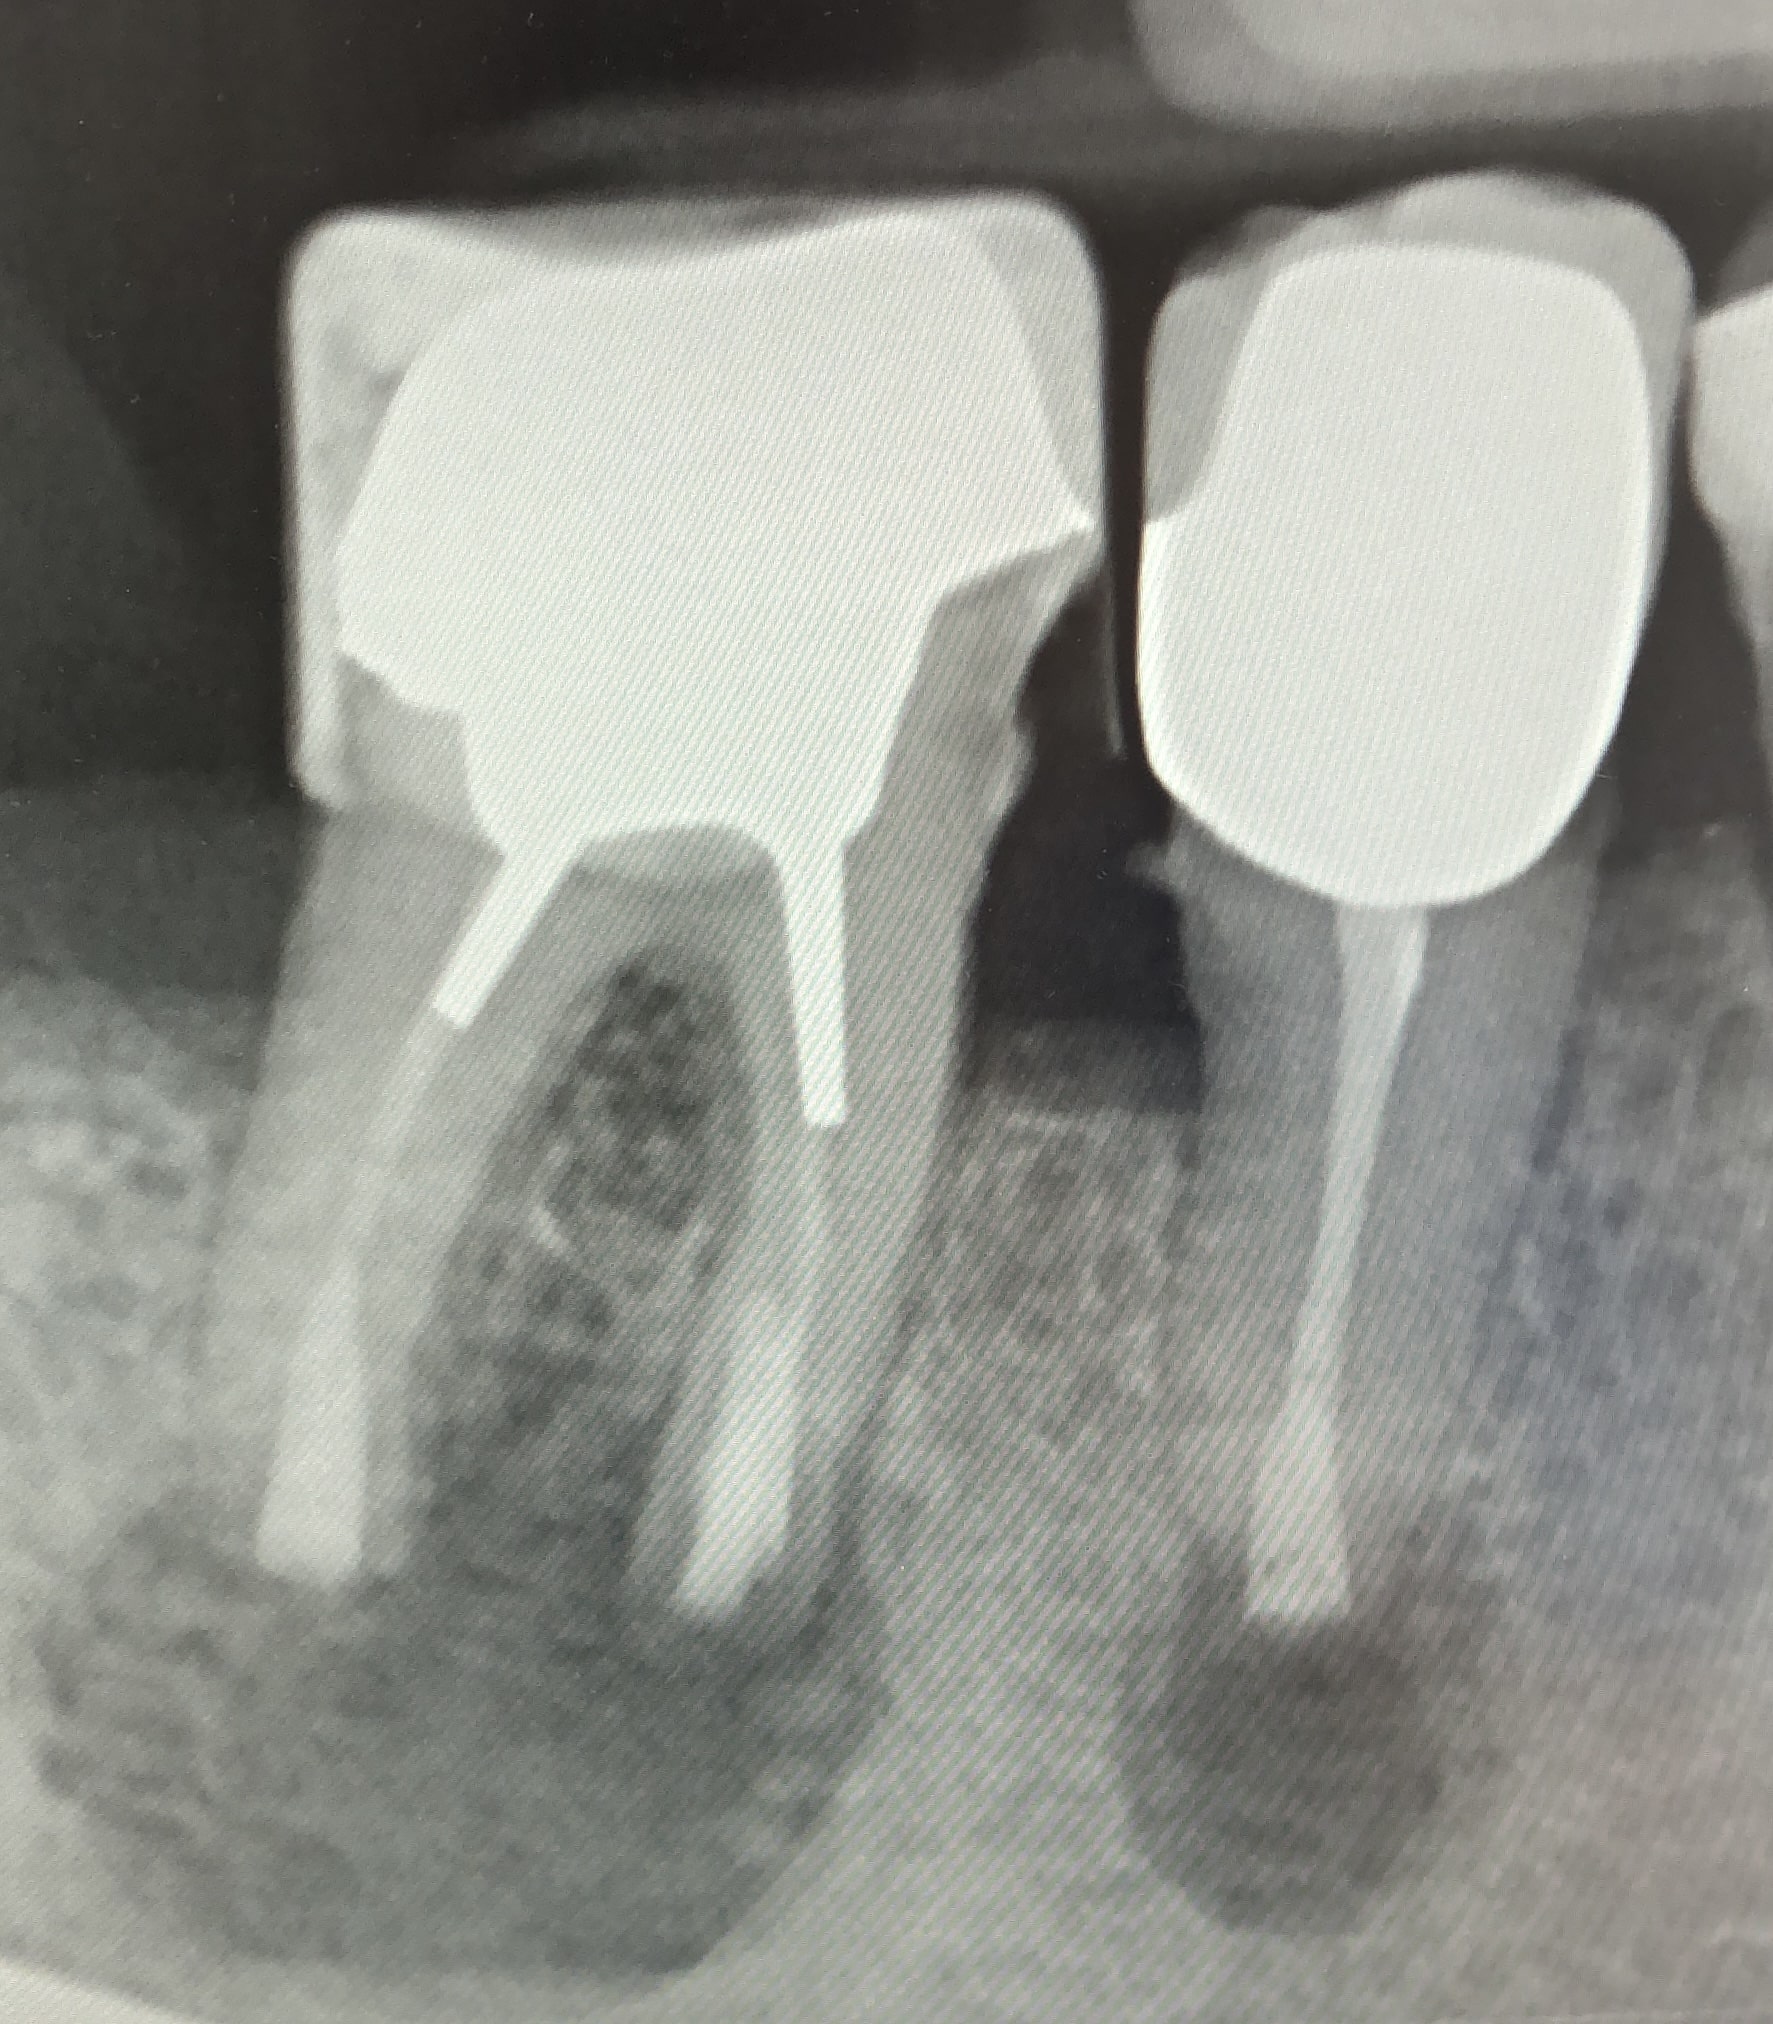

Zwei digitale Röntgenaufnahmen von Backenzähnen auf einem Monitor. Die Bilder zeigen Zahnwurzeln, Wurzelkanäle und den umgebenden Kieferknochen zur Beurteilung des Zahnzustands.

Vorher

Nachher